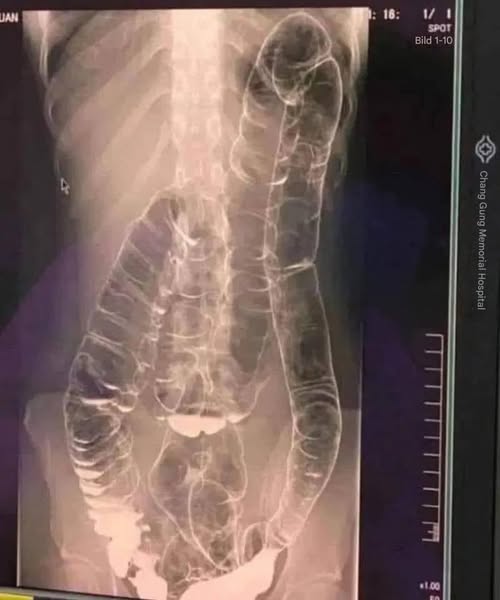

Wer kennt das nicht: Verstopfung. Dieses oft als harmlos empfundene Problem kann sich zu einem echten Albtraum entwickeln, wenn es ständig auftritt. Genau das passierte einer jungen Frau, deren überlasteter Darm sich gefährlich ausdehnte. Wie lässt sich also verhindern, dass diese Verdauungsstörung sich verschlimmert?

Bei unregelmäßigem Stuhlgang sammeln sich Abfallstoffe im Dickdarm an. Die Folge: zusätzlicher Druck, der Schmerzen, Blähungen und in schweren Fällen schwerwiegende Komplikationen verursachen kann.

- Darmüberdehnung: Mit der Zeit verliert der Dickdarm an Elastizität und die Stuhlentleerung wird zunehmend schwieriger.

- Darmverschluss: In extremen Fällen kann der Darm durch Fäkalien vollständig blockiert werden, was einen chirurgischen Noteingriff erforderlich macht.